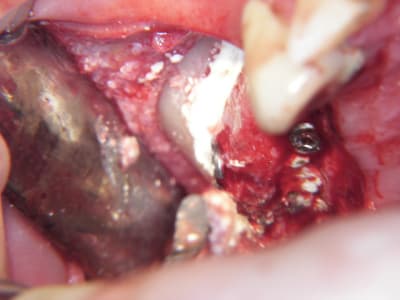

je viens de faire un sinus lift ce matin;

- 3 à 4 mm de hauteur sous sinusienne

- des cloisons de refend partout

- comblement avec du Vital Os

- un implant Axiom D4 L 10

comme je n'avais pas le temps de faire des photos la dernière fois et que j'en étais frustré, je me suis un peu lâcher aujourd'hui...

les premières photos, c'était ouverture par voie latérale